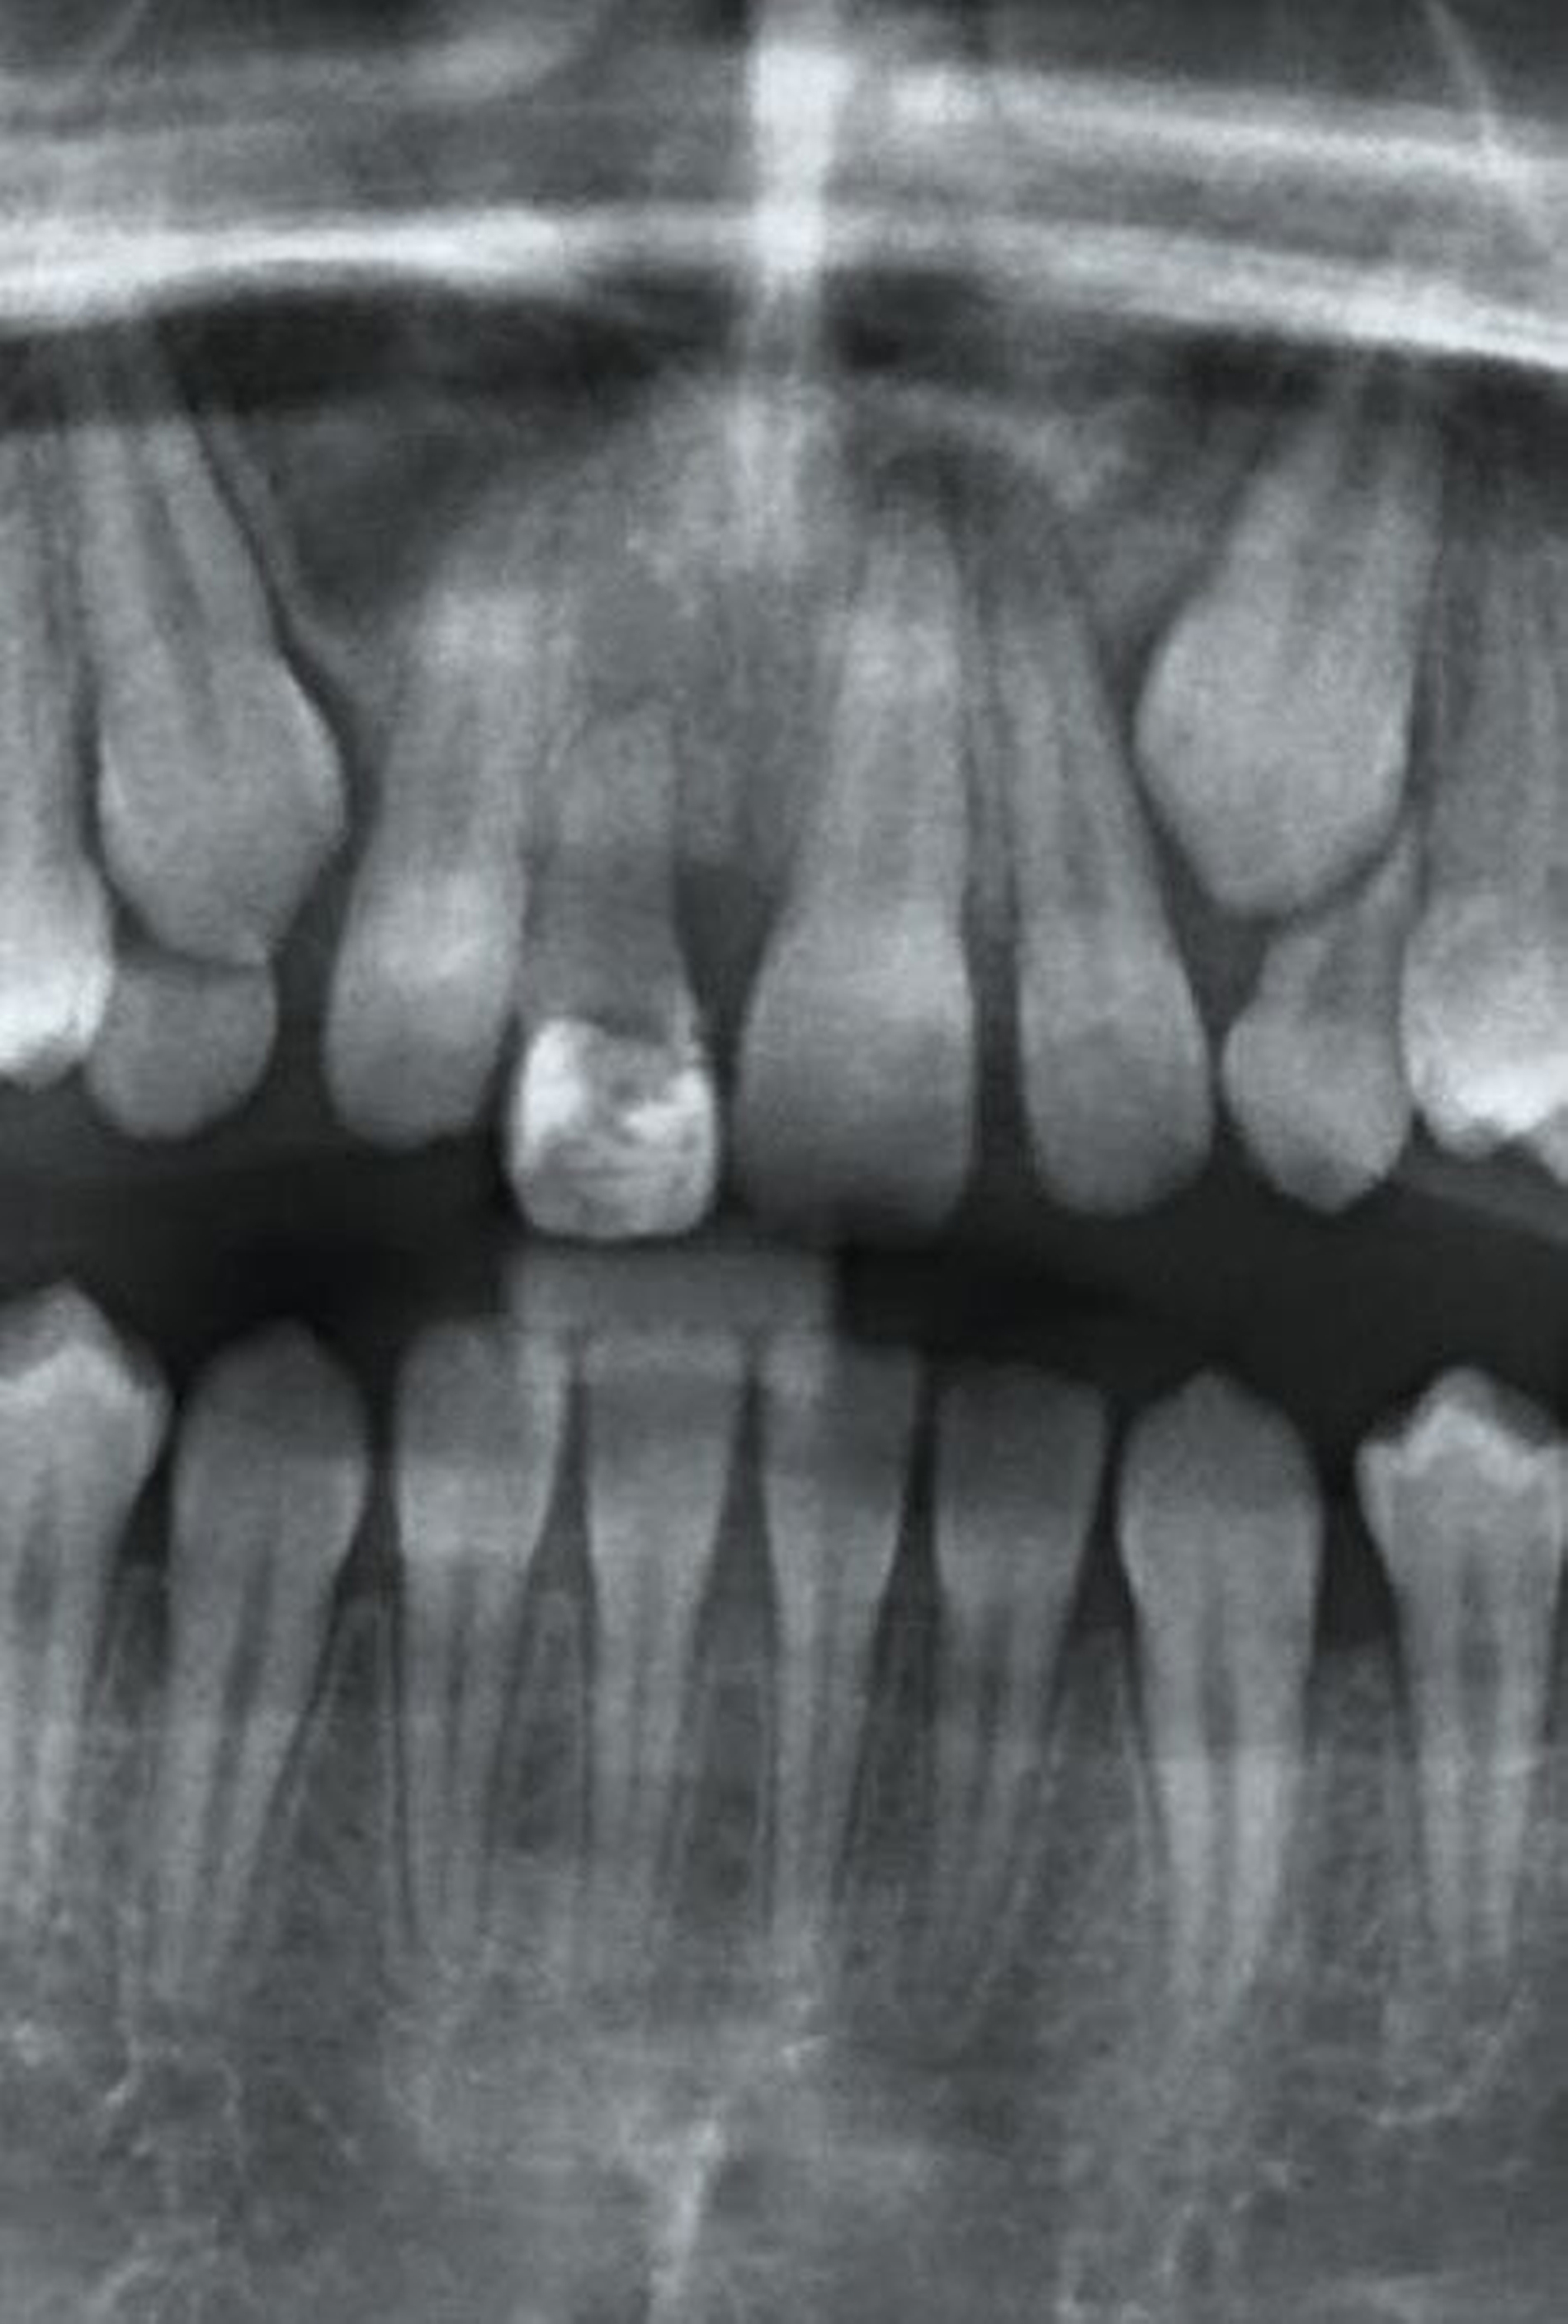

Abbildung 4 zeigt eine Milchzahn-Transplantation im frühen Wechselgebiss bei einem achtjährigen Mädchen bei nahezu vollständiger Ersatzresorption des Zahnes 11 nach Avulsion und Replantation. Trotz des sehr guten Zustands des Milchzahntransplants im Alter von zwölf Jahren entschied man sich in Rücksprache mit den Kollegen der Kieferorthopädie für die Prämolaren-Transplantation als eine zuverlässige Versorgung mit Überlebensraten von im Mittel 96,7 Prozent nach 8,75 Jahren [Akhlef et al., 2017]. Die Planung der Prämolaren-Transplantation sollte dabei immer in enger Absprache mit der Kieferorthopädie erfolgen, um zu klären, ob die Entnahme eines Prämolaren vertretbar und welche Entnahmestelle die geeignetste ist.